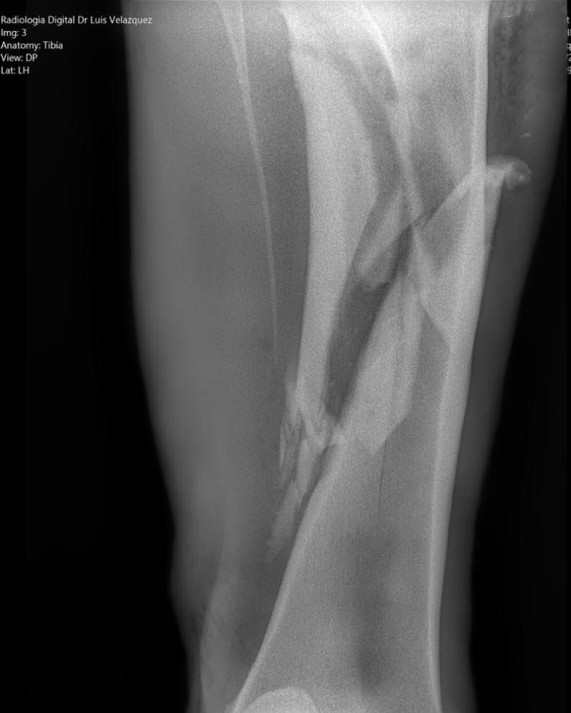

Radiología Digital como Herramienta Complementaria en el Dictamen de Bienes Muebles

Desde el descubrimiento de los rayos “X” y las placas radiográficas por Wilhelm Conrad Roentgen y su posterior difusión a través de la Asociación Físico médica de Wurzburg el 28 de diciembre de 1895, que fue la primera asociación que habló de los nuevos rayos que podían penetrar el cuerpo y fotografiar los huesos, ha habido muchos cambios tanto en la forma de obtener, procesar e incluso en la forma de visualizar, manejar y almacenar las placas radiográficas.